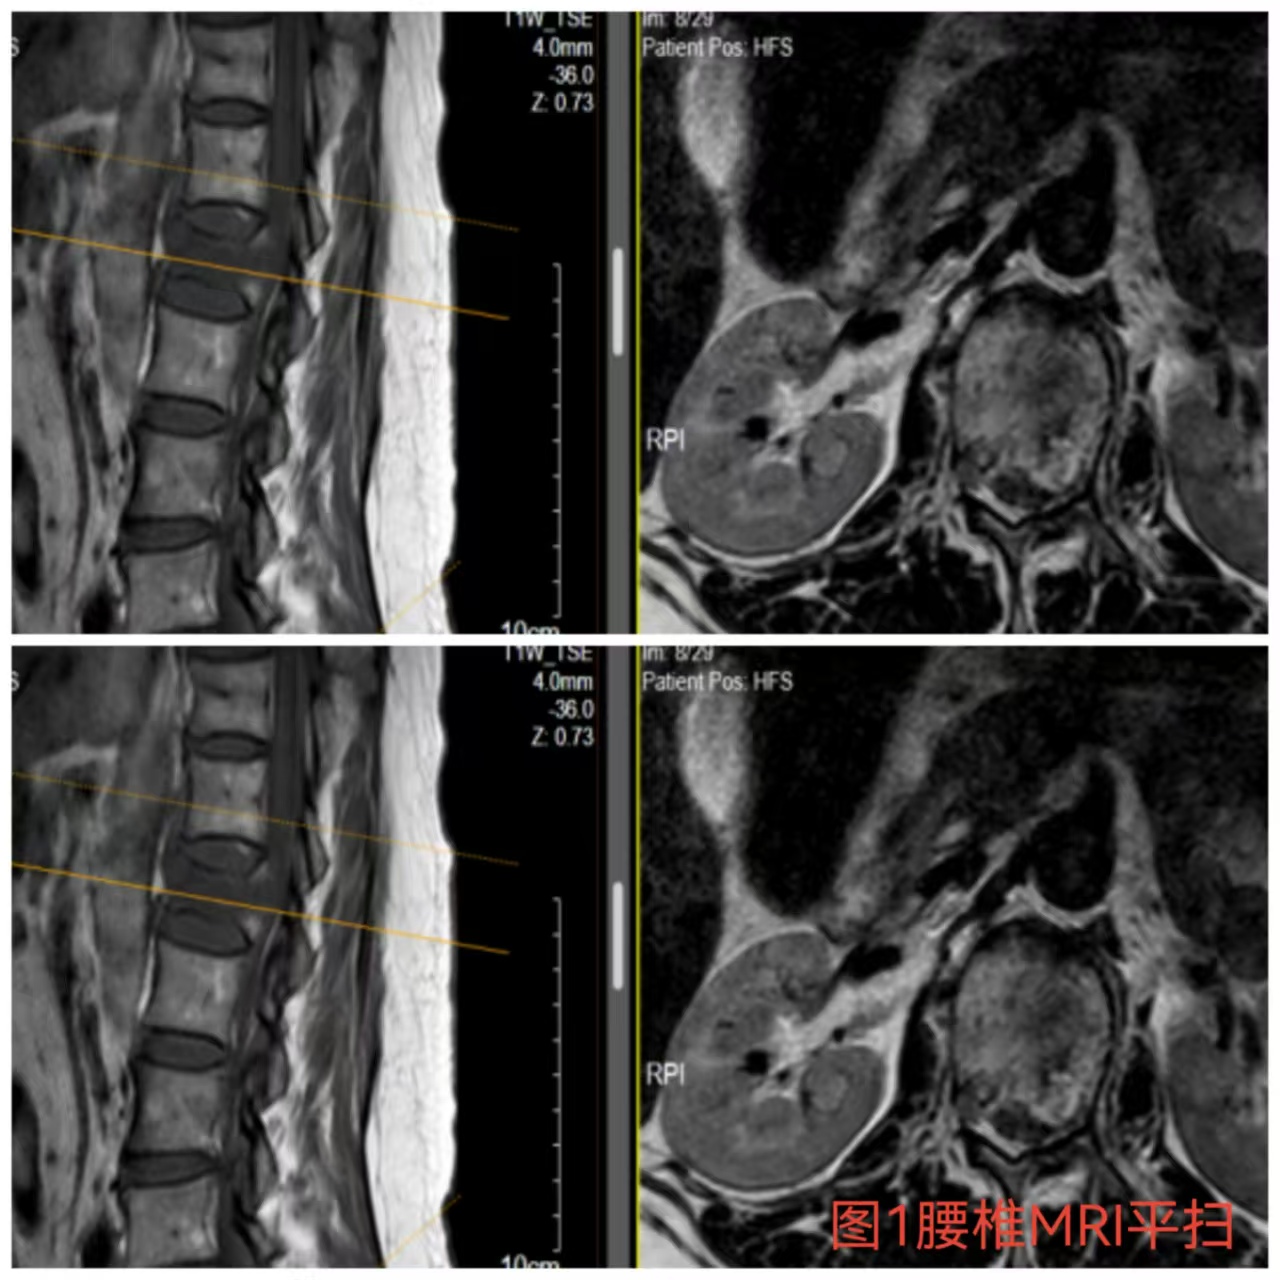

俞德亮副主任醫(yī)師深知病情的嚴(yán)重性,拖得時(shí)間越久,脊髓神經(jīng)損傷癥狀越難以恢復(fù),必須把握住早期減壓手術(shù)的關(guān)鍵時(shí)間窗,緊急帶領(lǐng)創(chuàng)傷骨科醫(yī)師團(tuán)隊(duì)對(duì)該病情進(jìn)行討論、制定手術(shù)方案,并成功為患者急診行“L1椎體爆裂性骨折伴截癱切開椎板切除+椎管探查減壓+骨折復(fù)位釘棒系統(tǒng)內(nèi)固定術(shù)(圖2)”,該手術(shù)精確解除對(duì)脊髓神經(jīng)的壓迫,并通過椎弓根螺釘內(nèi)固定系統(tǒng)對(duì)受損的腰椎提供穩(wěn)固的支撐,為后期的康復(fù)創(chuàng)造了良好的條件。